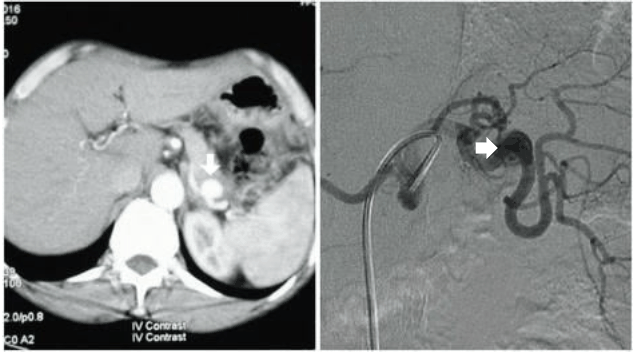

Mulher de 31 anos, nuligesta, em uso de anticoncepcional, assintomática, apresenta achado incidental de aneurisma visceral com 2,8 cm no maior eixo, apontado por setas nos exames abaixo. Sobre esse caso clínico, assinale a alternativa INCORRETA.